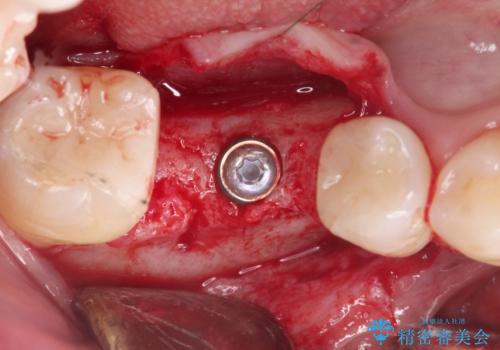

安定し、長く使用できるようなインプラント治療を実践するため、骨の増成をインプラント埋入と同時に行いました。